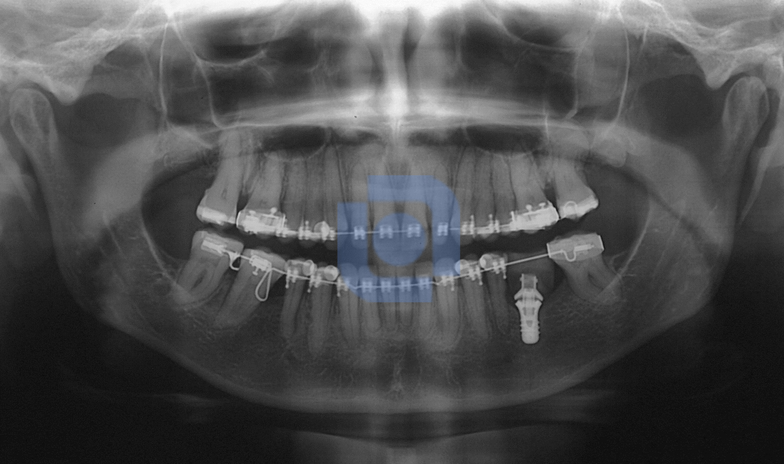

Intrusão de Molar com Mini-Placa de Ancoragem Esquelética

Mola de Verticalização de Molares